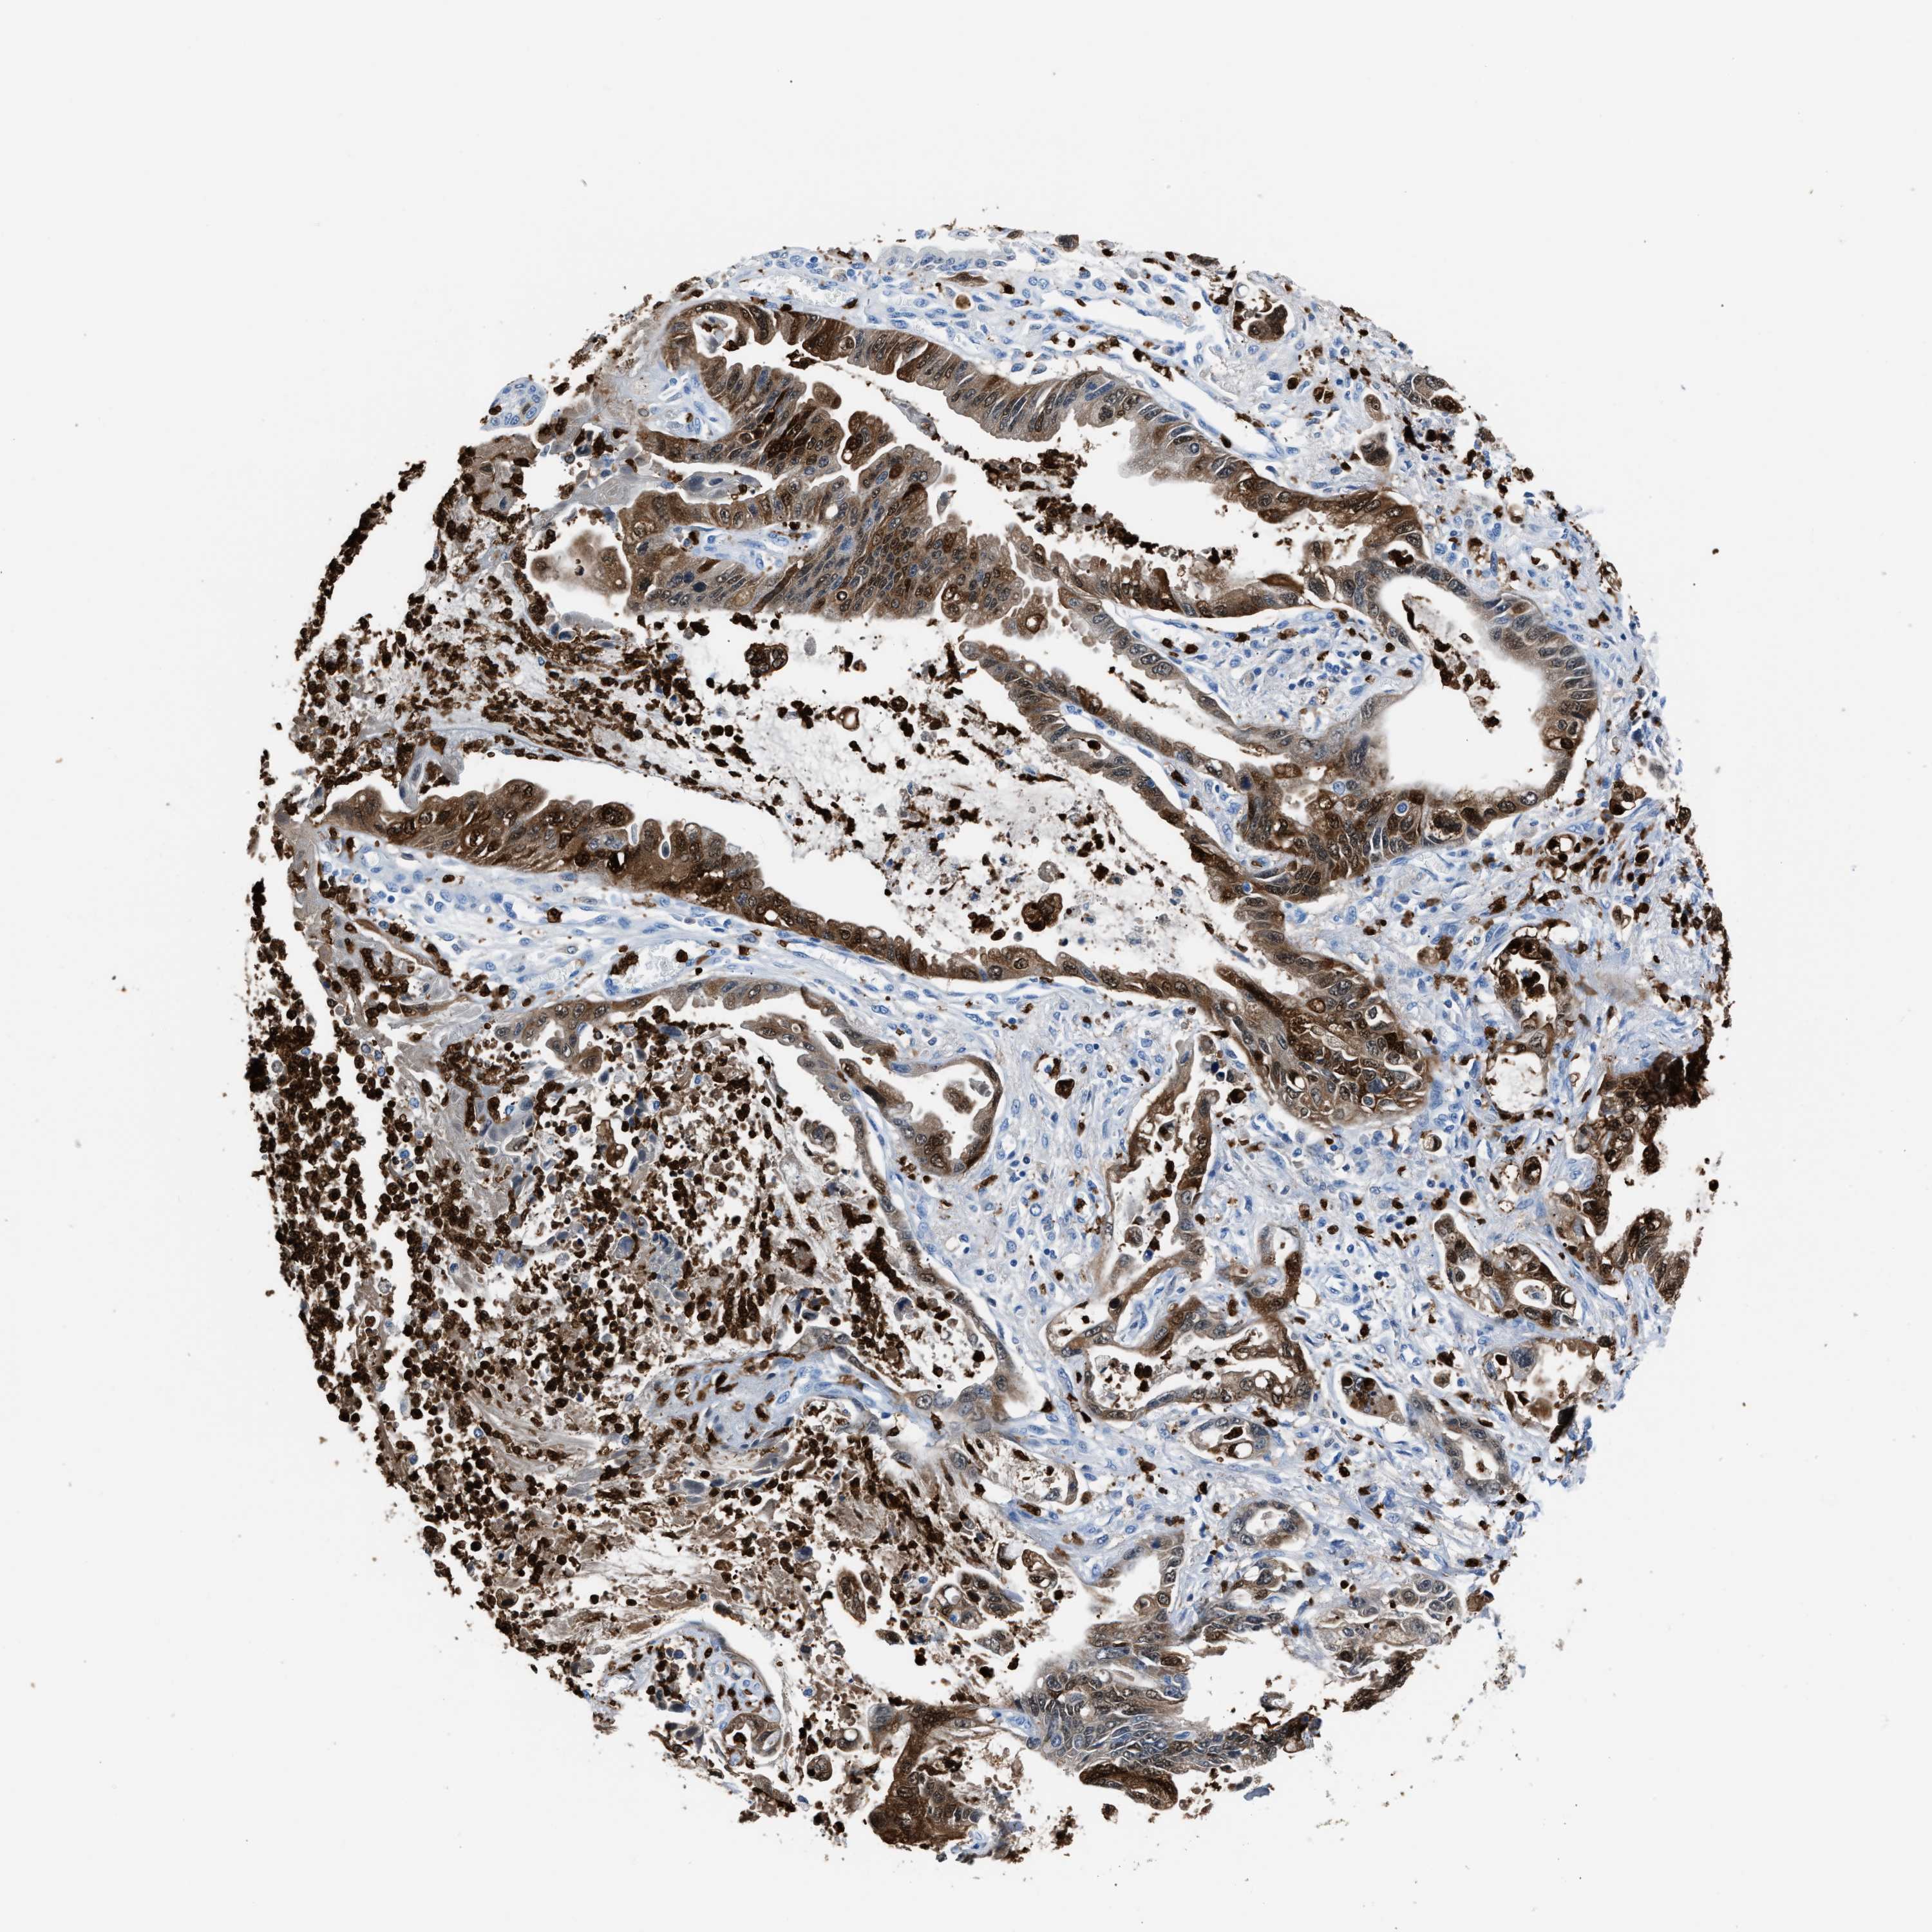

PANCREATIC CANCER - Protein expressioni

A mouse-over function shows sample information and annotation data. Click on an image to view it in a full screen mode. Samples can be filtered based on level of antibody staining by selecting one or several of the following categories: high, medium, low and not detected. The assay and annotation is described here.

Antibody stainingi

Antibody staining in the annotated cell types in the current human tissue is reported as not detected, low, medium, or high, based on conventional immunohistochemistry profiling in selected tissues. This score is based on the combination of the staining intensity and fraction of stained cells.

Each image is clickable and will lead to virtual microscopy that enables deeper exploration of all samples and also displays staining intensity scores, fraction scores and subcellular localization as well as patient and tissue information for each sample.

Antibody HPA019502

Staining

High

Medium

Low

Not detected

Intensity

Strong

Moderate

Weak

Negative

Quantity

>75%

75%-25%

<25%

None

Location

Nuclear

Cytoplasmic/membranous

Cytoplasmic/membranous,nuclear

Adenocarcinoma, NOS